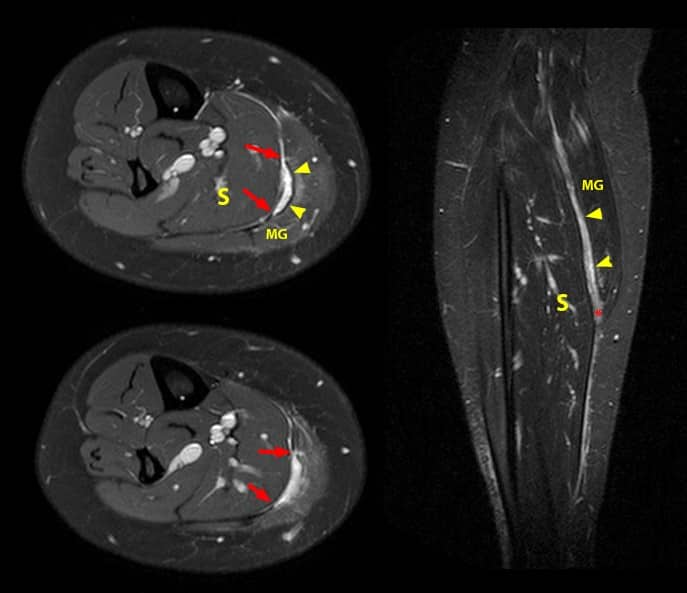

Calf Strain (Gastrocnemius) Grade II

| MRI - Right Calf |

Image Source: Image Courtesy of RadSource |